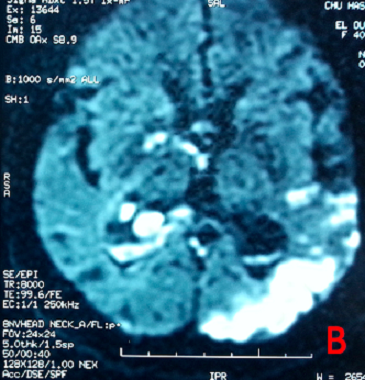

Meningite A Streptococcus Pneumoniae Et Vascularite Cerebrale Figure 1b

Figure Figure 3 Un Syndrome Malin Des Neuroleptiques Complique D Hemorragie Meningee Et Revelant Une Vascularite Cerebrale B

Figure 1 From Un Syndrome Malin Des Neuroleptiques Complique D Hemorragie Meningee Et Revelant Une Vascularite Cerebrale Semantic Scholar

Figure Figure 1 Un Syndrome Malin Des Neuroleptiques Complique D Hemorragie Meningee Et Revelant Une Vascularite Cerebrale B